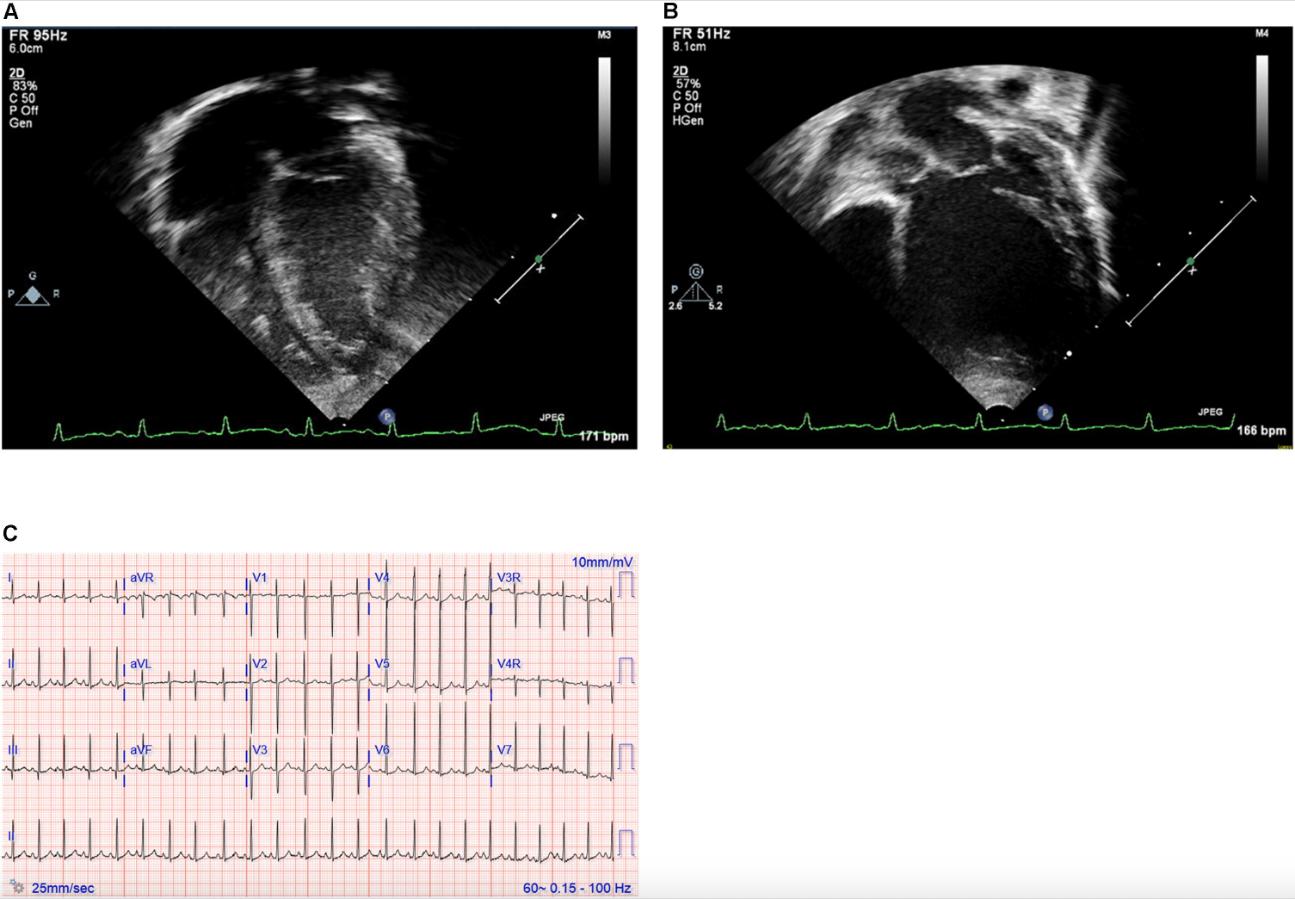

Figure 1. (A,B) Echocardiography images and (C) electrocardiogram. Still images obtained from echocardiogram of the proband at ages 2 weeks (A) and 12 months (B). Note particularly the progressive dilation and prominent rounding of the left ventricle (LV) in the later image. (C) Electrocardiogram at 19 months of age demonstrating sinus rhythm and left ventricular enlargement.